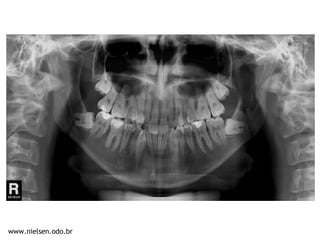

Classe I | Overbite | Mordida Cruzada Post-direita | Mordida Aberta 12/43

DM = - 10,2 mm Spee = -3 mm DC = - 1,6 mm IMPA 88°

42,6mm

27,9mm

XP 18, 28, 38 e 48